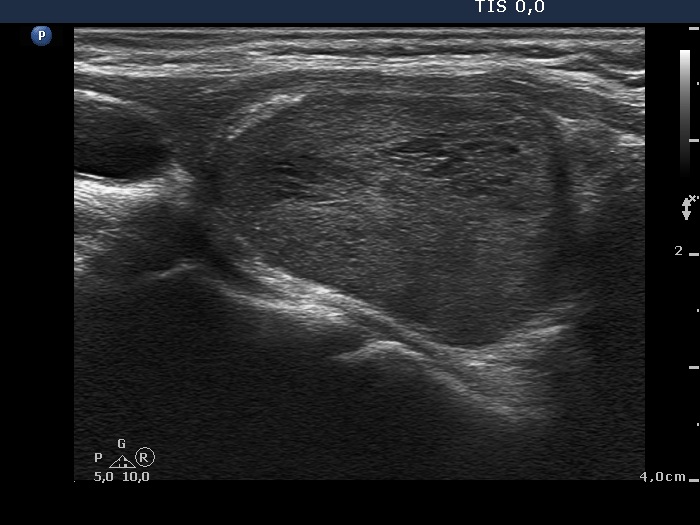

Clinical presentation: A 61-year-old woman was referred for follow-up evaluation. She has been know harboring an autonomously functioning nodule for almost 20 years. At the time of the diagnosis, the diameters of the nodule were 12, 11 and 13 mm, width, depth, and length, respectively. She has been always euthyroid and had never got any thyroid medication. The nodule had increased slowly but continuously over the decades.

Ultrasonography. The thyroid was echonormal. There was a moderately hypoechogenic nodule in the right lobe. The lesion displayed halo sign and perinodular blood flow.